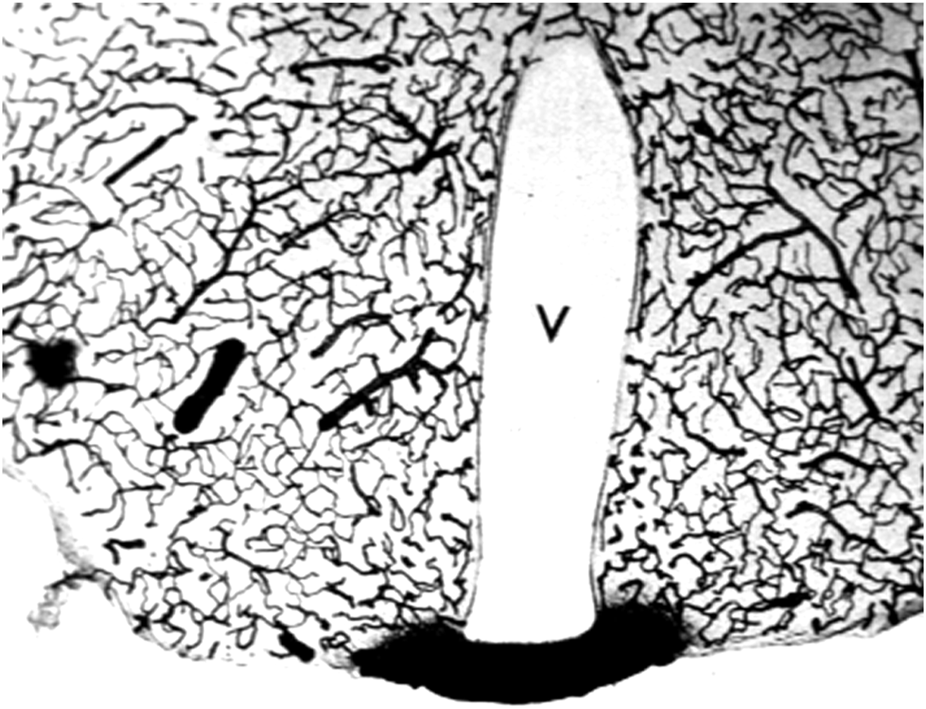

Aducanumab was said to cross the intact BBB, because the brain concentration of the antibody was higher following the administration of a high injection dose (ID) as compared to the brain concentration of antibody following administration of a low ID (Sevigny et al, 2016). The aducanumab brain volume of distribution (VD), which is the ratio of the brain concentration, in ng/Gram, divided by the plasma concentration, in ng/uL, was only ∼1 uL/Gram, following washout of the brain (Sevigny et al, 2016). That is, the brain concentration of aducanumab was 1,000-fold lower than the plasma concentration. The brain VD of aducanumab, 1 uL/Gram, is 5% of the brain plasma volume in the mouse, which is ∼20 uL/g (Boswell et al, 2014). Therefore, this brain aducanumab concentration would be expected if 5% of the plasma volume was retained in brain following washout of the vasculature. If a therapeutic antibody, or any drug, is retained in brain within the plasma volume, then that drug is present in brain, per se, but has not crossed the BBB. This is illustrated by the histochemistry of mouse brain following the IV administration of horseradish peroxidase (HRP), as shown in Figure 3. HRP is a 40 kDa protein that does not cross the BBB, and does not enter brain, except in tiny regions of the brain, designated circumventricular organs (CVO), which lack a BBB (Miyata, 2015). One CVO is the median eminence at the base of the third ventricle, and the uptake of HRP in this region of brain is shown in Figure 3. If a homogenate of the brain shown in Figure 3 was prepared, then HRP would be measurable, and it might be concluded that HRP crosses the BBB, providing the role of the brain plasma volume was not considered. The role of the brain plasma volume (Vo) can generally be ignored in the development of small molecule drugs that have a VD in brain that is high relative to the Vo. However, in the case of drug development of biologics, where the brain VD approximates the Vo, it is crucial to account for drug sequestration in the plasma volume of brain, before concluding that a given biologic crosses the BBB. If the brain VD of a therapeutic antibody is not greater than the brain plasma volume, Vo, then the antibody does not cross the BBB.

FIGURE 3

The brain plasma volume is illustrated in this coronal section of mouse brain after the IV injection of horseradish peroxidase (HRP), a 40 kDa protein that does not cross the BBB. Four tiny areas of brain, circumventricular organs (CVO), lack a BBB (Miyata, 2015), and one CVO, the median eminence at the base of the third ventricle (V), is shown in this section. The HRP is sequestered within the plasma compartment of brain without passage across the BBB. However, if a homogenate of brain was produced, then HRP in brain would be measurable. This image is a kind gift of Dr. Milton W. Brightman, and is reproduced from Pardridge (2022b).